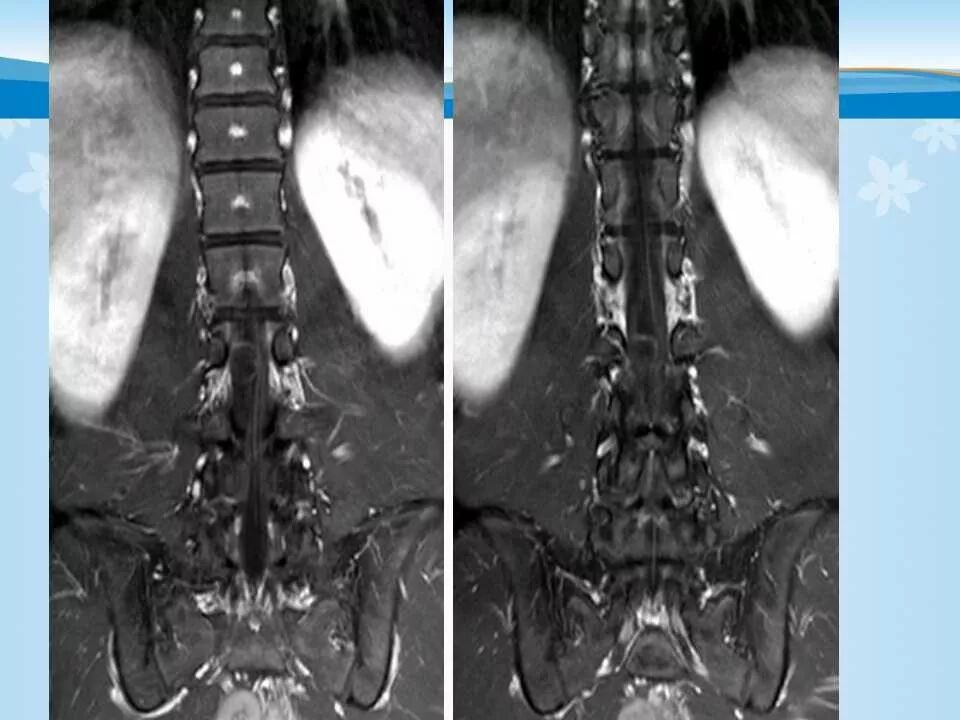

北方影像联盟 一周病例精选之“椎管占位”